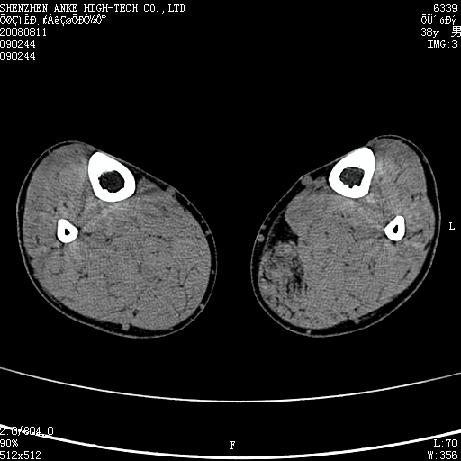

标题: CT15117:M38Y,小腿平扫 [打印本页]

标题: CT15117:M38Y,小腿平扫

患者,男,38岁,右小腿疼痛性包块1月,查体:右小腿可扪及约5x4cm大小包块,压痛.

左小腿内侧软组织病变,性质待定(血管瘤?);建议行mri检查。